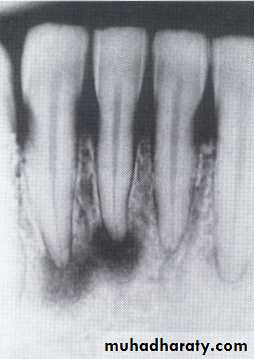

Histiocytosis-X (Langerhans cell disease):They are three manifestations produce tumour-like lesions in bone, caused by proliferation of Langerhans cells and eosinophilic leucocytes.

Radiographically :

• Multiple radiolucent areas in the interdental & interradicular bone.

• teeth seem to hang in air. Exfoliation of teeth & teeth germ are common, ulceration of overlaying mucosa.